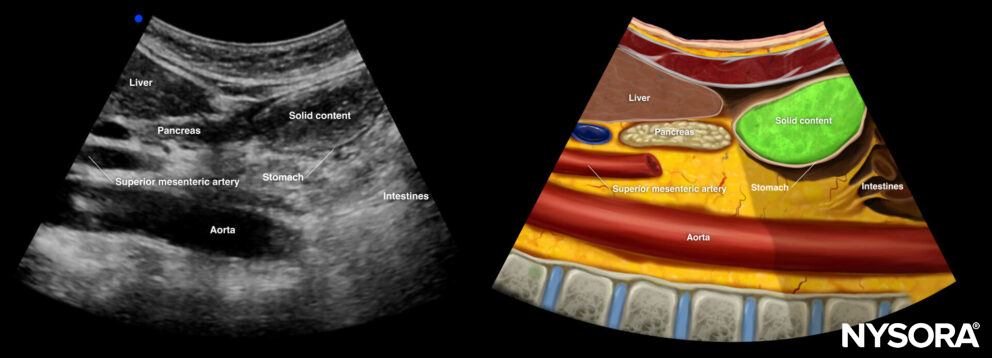

Solid content: Late phase

After a couple of hours, the air will disappear, and the content will be better outlined as gastric content with a mixed echogenicity.

Ultrasound and Reverse Ultrasound Anatomy of a stomach with solid content in the late phase.